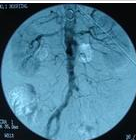

2.肺動脈造影

肺動脈造影是確診肺動靜脈瘤的可靠方法,肺動脈造影可明確病變部位,形態,累及的範圍及程度,為臨床治療方法的選擇提供依據,造影方法分為選擇性或超選擇性肺動脈造影,一般先進行選擇性主肺動脈造影。

動脈血氧飽和度下降,心搏出量和心腔壓力正常也無心內分流存在,顏料稀釋試驗可用於測試分流量和部位,注意避免導管進入瘺內,警惕破裂危險,在肺動脈注射造影劑可顯示動靜脈瘺的部位和大小,可見擴張,伸長,扭曲的血管。